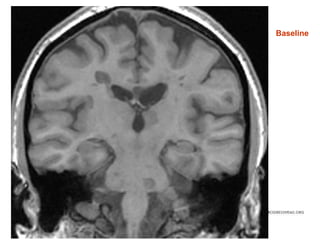

Baseline

• #41 Baseline scan (native space)